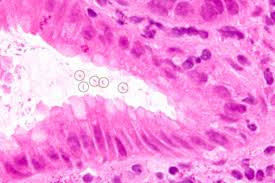

胃幽门螺旋杆菌(H.Pylori)入侵